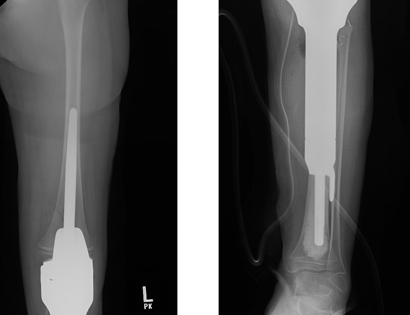

This is an x-ray image of the tibial prosthesis post-surgically.

The prosthesis is inserted to match the length of the diseased bone removed and the prosthesis joint is attached to the upper femur bone.